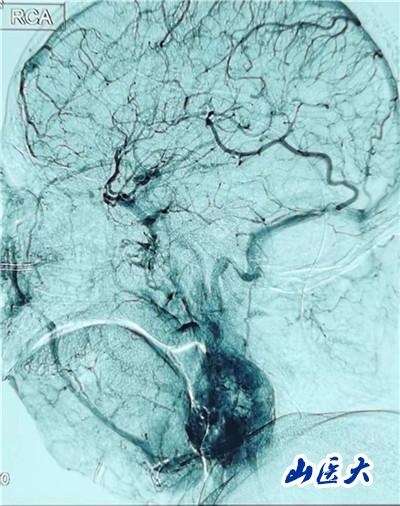

患者入院后,医院成立了由口腔颌面外科、神经外科、血管外科、介入科、麻醉科、手术室组成的多学科团队,对患者的病情进行反复研究,对手术方案进行多次探讨。先由介入科杨敏玲主任医师团队对患者实施了颈动脉血管造影术,对肿瘤的血供情况进行详细掌握;神经外科郭庚主任医师团队术前对患者进行了颈内动脉暂时性球囊阻断试验,对患者的脑缺血耐受性进行了科学评估。由医务处牵头又进行了全院大会诊,制定了多套手术方案并对手术流程进行了反复梳理,准备了颈动脉修补—颈动脉人工血管重建—颈动脉覆膜支架置入等该领域最新技术手段。